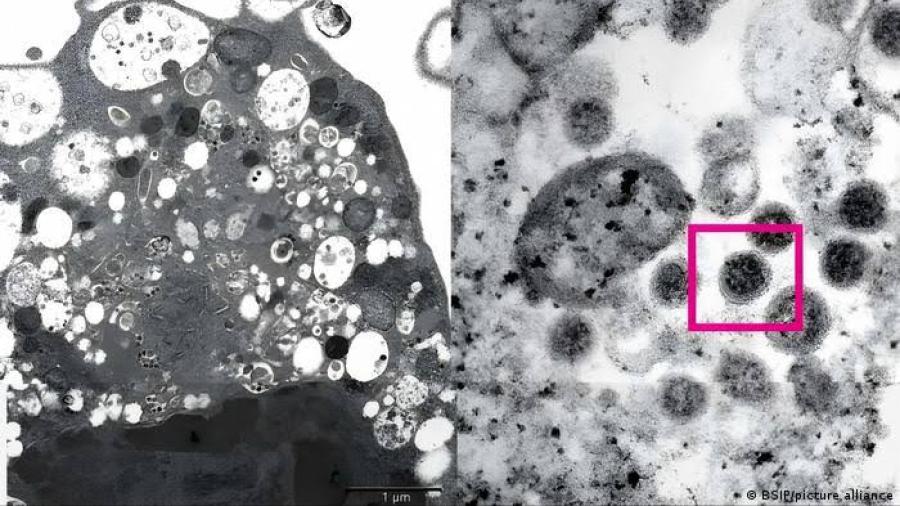

Detectan primer caso de subvariante Ómicron BA.2 en México

De acuerdo con el Instituto Nacional de Medicina Genómica (INMEGEN), se detectó en México el primer caso positivo de la subvariante BA.2 de Ómicron, la más contagiosa según algunos estudios y que se plantó en una mujer de 48 años de edad.